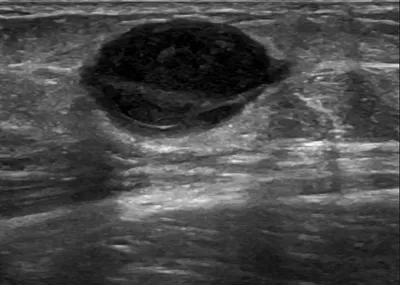

- This collection contains 4 radiology images related to forearm, including various imaging modalities such as X-rays, MRIs, CT scans, and ultrasound images commonly used in medical diagnosis and education.